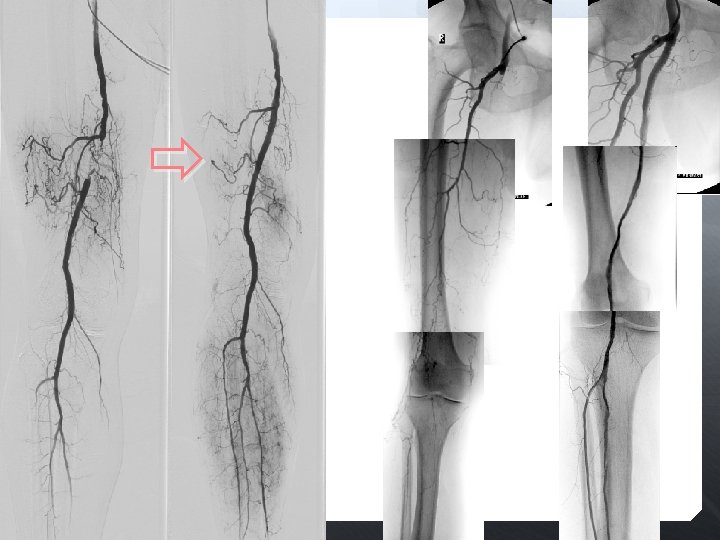

SFA

Re-entry cihazı